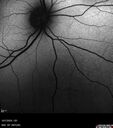

BRAO - plaques in vessels - GIF video of FA3 views78 year old female with vision loss for 1 week and old macular scar. Images show BRAO with plaques and FA shows occlusion.Oct 13, 2025